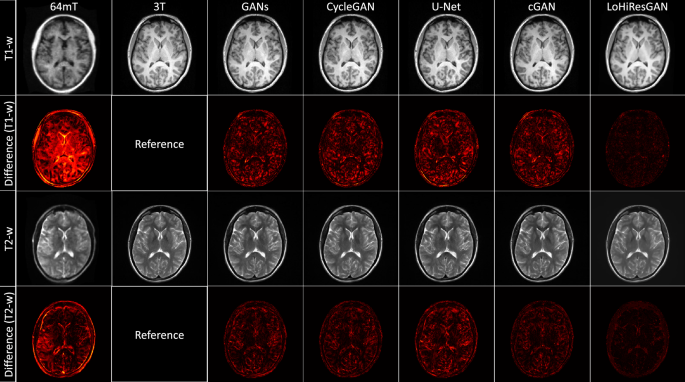

Figure 1 shows substantial qualitative disparities between representative 64mT and 3T images in both T1-weighted and T2-weighted modalities. These visual differences among the 64mT, GANs, CycleGAN, U-Net, and cGAN images are minimized by LoHiResGAN. An absolute difference image is also computed for each method’s output, demonstrating the variation in translation results between these methods. This shows the residual signal error compared to 3T and is clearly lowest for LoHiResGAN.

Comparison of T1-weighted and T2-weighted images (32-year-old male participant) and their absolute difference (plotted in the range of [0, 1]) with respect to 3T reference images across various state-of-the-art image-to-image translation techniques. From left to right: 64mT, 3T, GANs, CycleGAN, U-Net, cGAN, and LoHiResGAN.